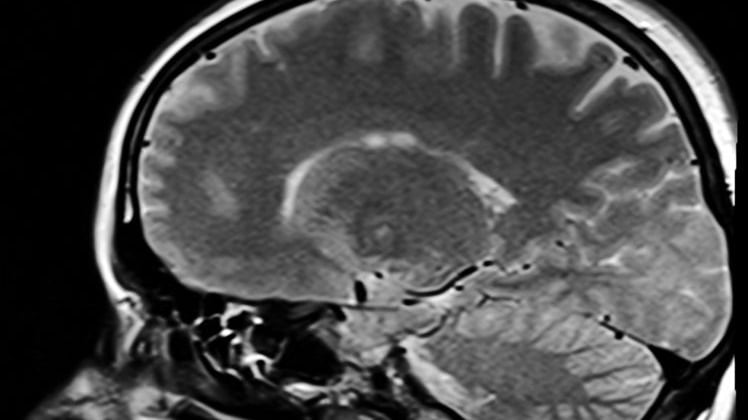

4) Hirnschäden

Ähnlich könnte es sich bei Hirnschädigungen durch Unfall oder Krankheit verhalten. Ein Parkinson-Patient mag auf Bewusstseinsebene die Absicht hegen, sich kontrolliert zu bewegen. Das Bewusstsein sendet entsprechende Aufforderungen an das Gehirn. Dieses ist aber krankheitsbedingt nicht mehr in der Lage, der Aufforderung Folge zu leisten. Das gleicht einer Situation, in der ein Bildschirm wegen eines technischen Defekts kein scharfes Bild mehr erzeugen kann, obwohl der Computer alle Informationen schickt, die es dafür bräuchte.

Bei Alzheimer-Patienten schwinden Erinnerungen. Im schlimmsten Fall vergessen sie ihre eigene Biografie und erkennen selbst ihre engsten Verwandten nicht mehr.

Vom Gedächtnis haben wir weiter oben behauptet, es befände sich nicht im Gehirn, sondern im Bewusstsein. Die Alzheimer-Erkrankung gleicht darum keiner Beschädigung der Festplatte auf dem Computer, sondern einer Beschädigung am Monitor. Textinformationen, Bilddateien und Videoaufnahmen könnten demnach nicht mehr richtig am Bildschirm widergegeben werden. Auf den Alzheimer-Patienten bezogen bedeutet das: Sein Gehirn kann auf die Daten, die im Bewusstsein gespeichert sind, nicht mehr richtig zugreifen.

Für unser Modell des Gehirns als Sender und Empfänger für ein externes, metaphysisches Bewusstsein gilt also ganz allgemein: Krankheiten und Unfälle, die das Gehirn schädigen, beeinträchtigen niemals das Bewusstsein! Sie schränken nur dessen Wahrnehmungs- und Ausdrucksmöglichkeiten ein, weil aufgrund der Beschädigungen an der Sende- und Empfangseinheit (Gehirn) falsche oder keine Informationen an das Bewusstsein gesendet werden oder weil Informationen, die vom Bewusstsein ausgehen, nicht beziehungsweise nur schlecht empfangen und übersetzt werden.